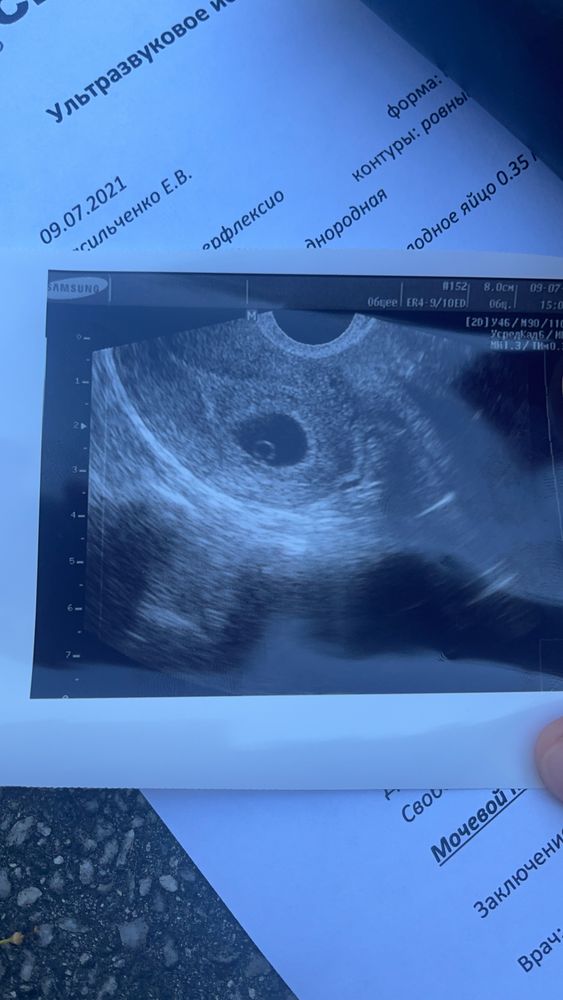

Наконец-то наше чудо с нами! Вторая беременность и ребёнок - те же эмоции?